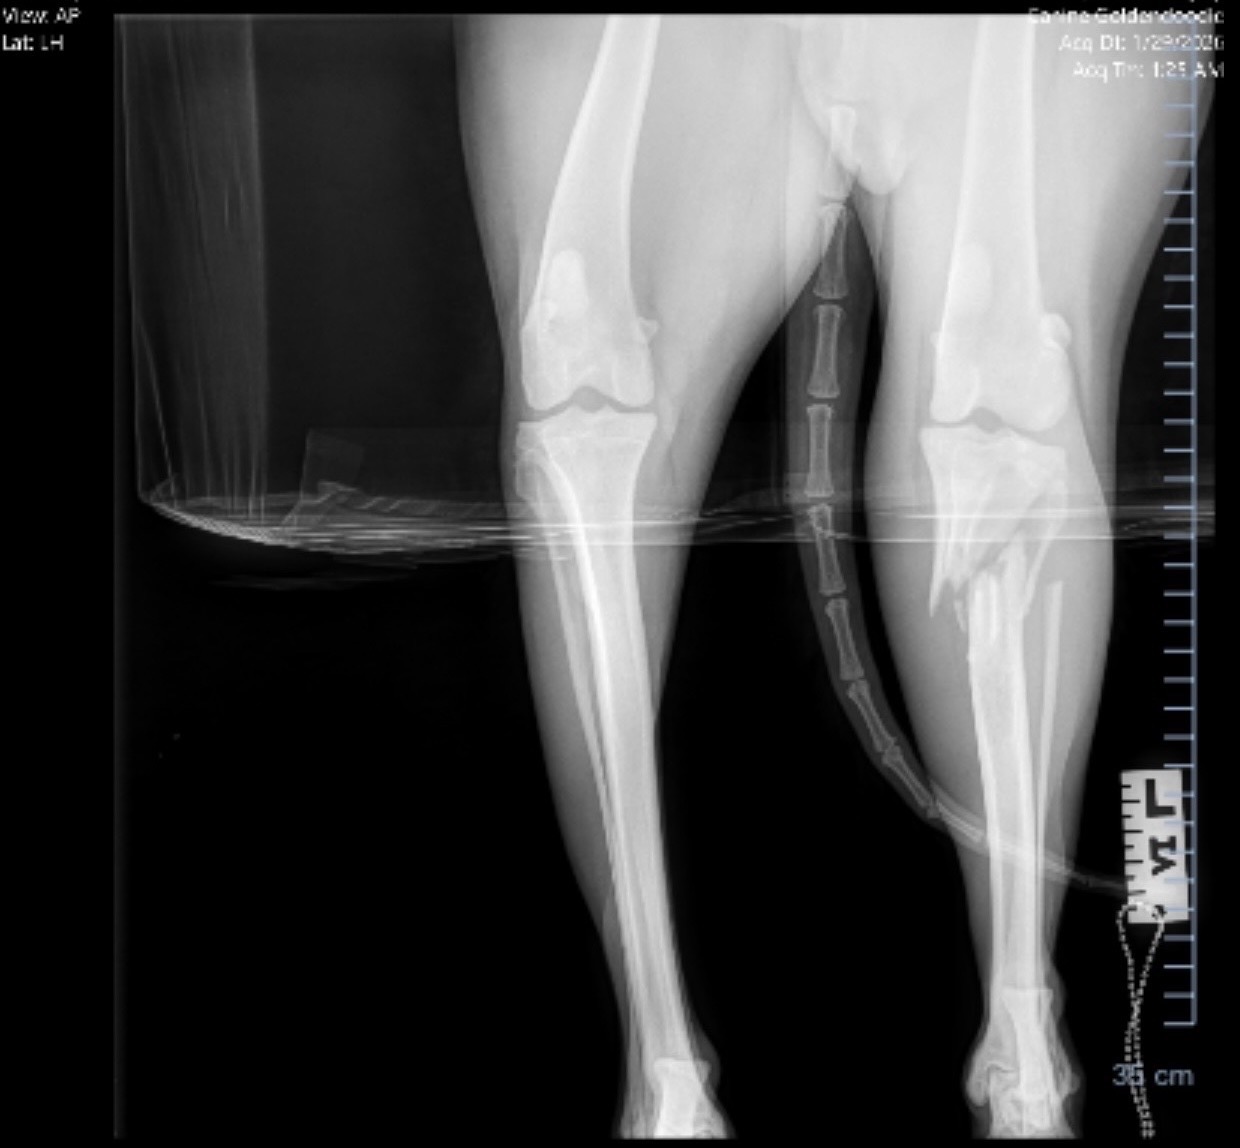

A few days ago, Wrigley’s world was turned upside down when he suffered a shattered leg. I’ve already spent $1,500 on emergency care just to get him stable and on pain management, but the hard part is just beginning. He needs surgery immediately to either repair the fracture or perform a life-saving amputation.

• Surgery (either a plate to repair the bone or an amputation)

• Biopsy to confirm if there is underlying bone disease